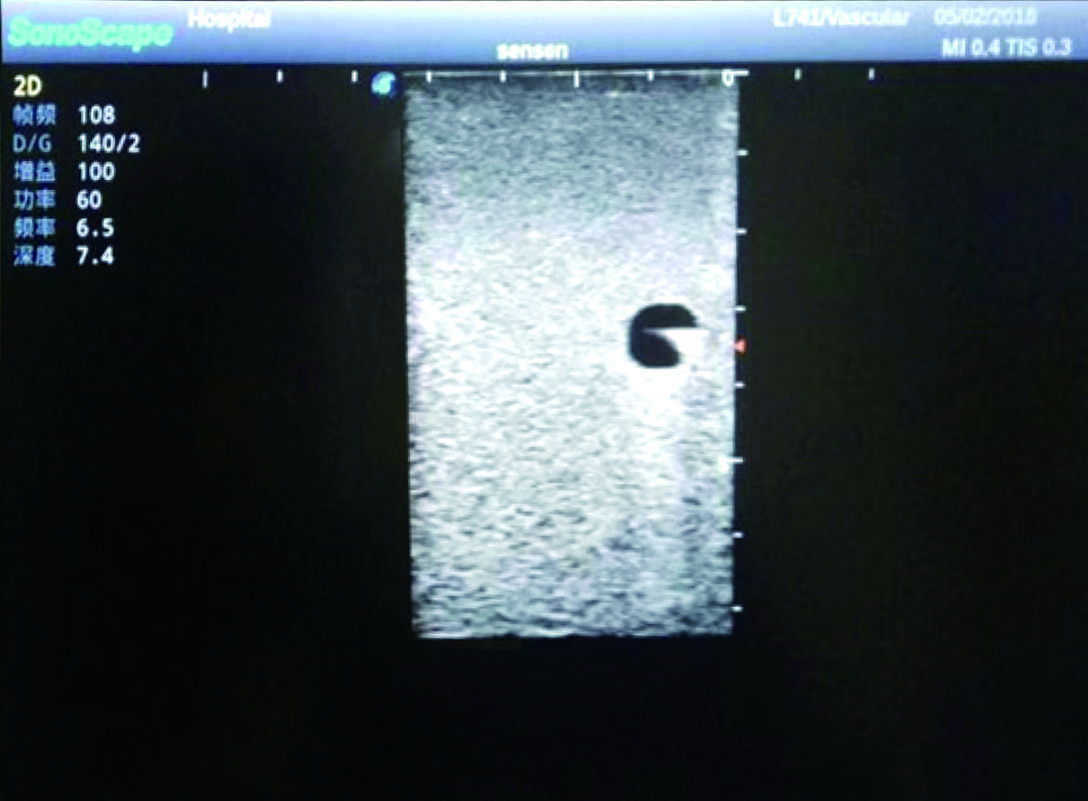

2)   It can be used by real ultrasound machines

3)   Clear and real images of the tissues and organs (basilic vein and superior vena cava)

4)   When conducting vascular puncture, the piercing can be truly felt, and venous blood outflow can be seen

5)   Observe the guide wire marches

6)   Detect whether the catheter is properly placed